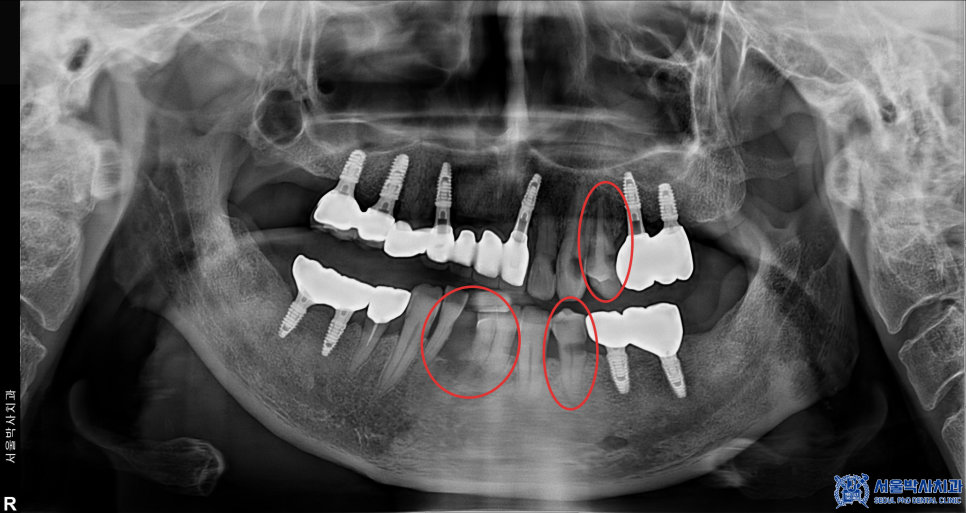

앞니가 빠진 부위뿐만 아니라 전체적으로

상태가 좋지 않은 치아들이 많았고,

몇몇 치아는 염증이 심한 상태였습니다.

치료를 위해 이미 빠져있던 치아 이외에 문제가 심했던

왼쪽 위 작은 어금니, 왼쪽 아래 작은 어금니,

아래 앞니 2개 총 치아 4개를 발치한 후,

임플란트를 식립하기로 결정했고

특히 아래쪽 앞니 부위는 오랜 기간 치아가

빠져 있던 탓에 뼈가 많이 흡수된 상태였습니다.